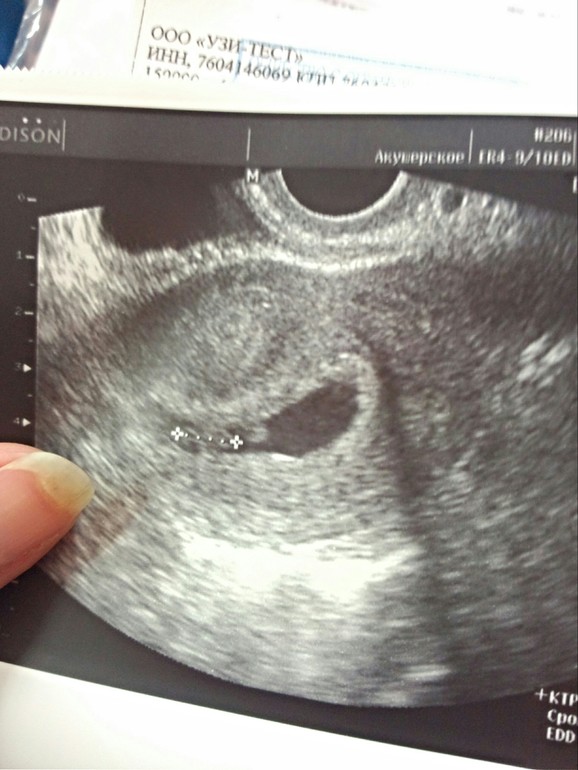

Нет, он малюсенький был еще)))) горошинка! Зато при увеличении показали сердесную трубку и сердцебиение — как же я рыдала)))) этот момент не забуду никогда! Вот мы на первом узи! Тут нам ктр измеряют) 674240961242ee0f8323e179c5499f91.jpg